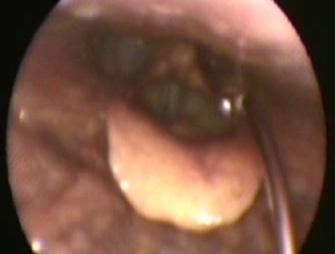

• percutan tirohioidian, cu ac de 23 G dublu angulat manual. Avantaje: vizualizarea optimă a versanului superior al corzilor vocale; nu se pierde substanță în spațiul mort; dezavantaje: devierea acului la pacienții seniori și/sau cu „gât gros”, ceea ce face ca această metodă să nu fie ideală pentru începători (pătrunderea repetată în lumen va determina o ușoară sângerare ce va împiedica vizualizarea optimă ulterioară a situsului de injectare);

• percutan cricotiroidian (Fig. 4), cu ac de 23 G angulat o singură dată manual. Avantaje: cel mai ușor de pătruns în lumenul respirator; nu se pierde substanță în spațiul mort al acului; Dezavantaj: vizualizarea mai dificilă a versantului inferior al corzilor vocale.

Efecte adverse/complicații ale injectărilor de augmentare: hematom, migrare în țesuturi regiuni anatomice adiacente, granulom, stridor, reacție inflamatorie sau de intoleranță la substanță (1,2) . Injectările de toxină botulinică